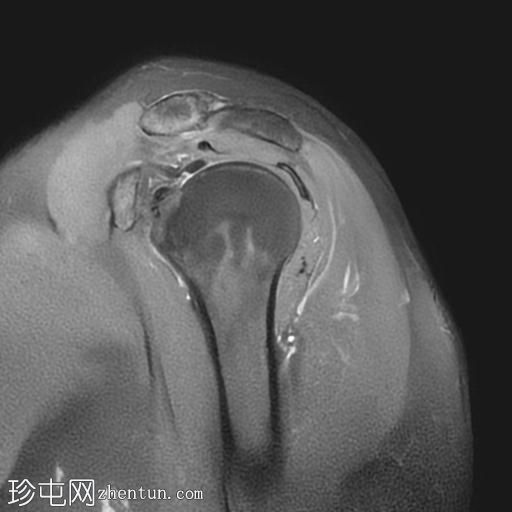

轴位PD序列

冈上肌腱中后部关键区及肌腱止点纤维可见一低信号椭圆形病灶,大小约5 x 8 x 16 mm,提示钙化性肌腱炎。

肩锁关节轻度关节囊肥厚及退行性改变。

肩峰类型:II型